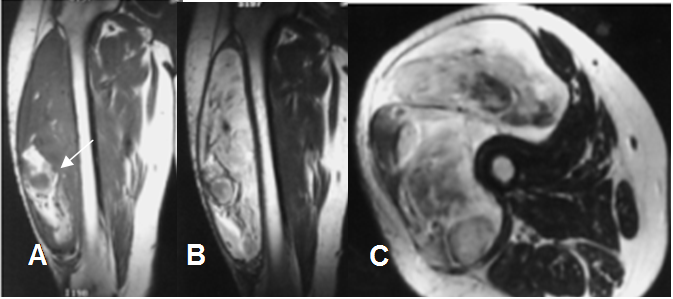

Fig 172. Liposarcoma.

A: RM coronal en T1. Lesión de tejidos blandos, con zona hiperintensa en la parte inferior, por contenido graso.

B: RM coronal en T2. Extensa lesión heterogénea en la parte externa del muslo.

C: RM axial en T2. Lesión heterogénea de comportamiento agresivo, con infiltración de los músculos del compartimiento anterior y lateral, por liposarcoma.